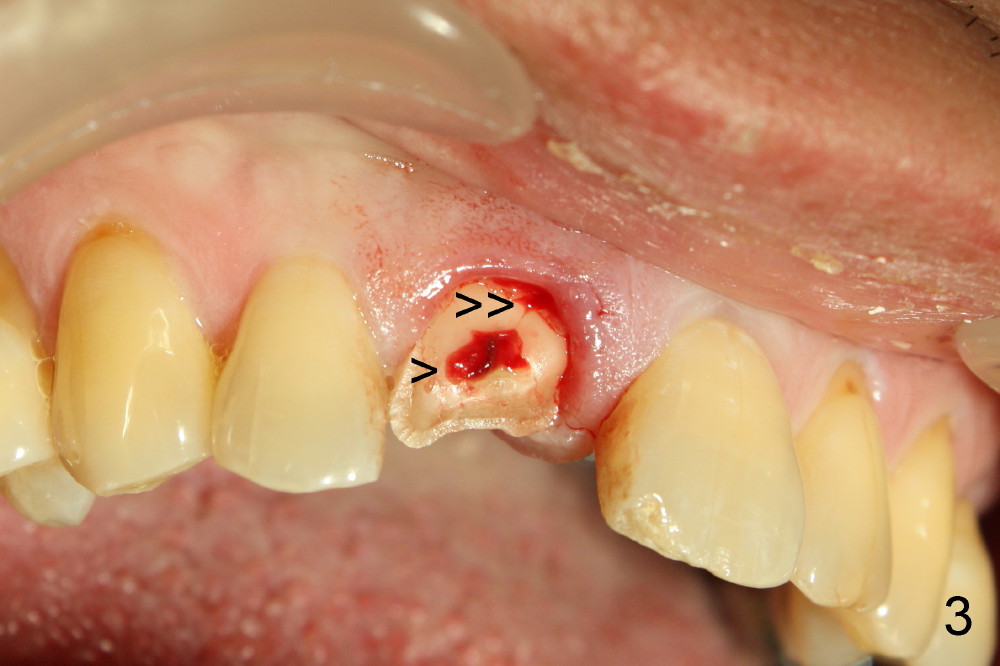

A 55-year-old man has severe pain on the upper right central incisor (Fig.1 *) after biting on a piece of bone. PA confirms crown fracture (Fig.2 <), extending subgingivally (Fig.3 >>). Osteotomy forms using a 2 mm pilot drill and 2.5-3.5 mm reamers (Fig.4). A 5x17 mm Tatum tapered implant is placed, autogenous bone placed in the buccal gap, sutures placed for wound approximation and 3.5 mm 20º angled abutment installed (Fig.5). An immediate provsional is fabricated (Fig.6), cemented and splinted (Fig.7).,